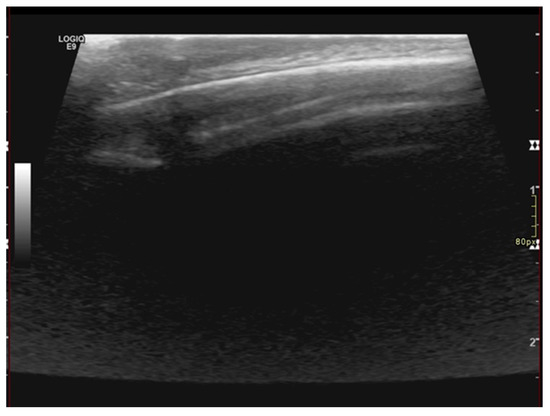

Figure 2.

U/S of the scalp lesion showing thickening epicranial tissues without alteration of the echostructure and absence of focal lesions. The thickness of the skin fold is 6 mm. Brain U/S investigation did not reveal any abnormality of the posterior cranial fossa and of the encephalic tissue. U/S of the skin fold and scalp showed regular soft tissue appearance and normal bony structures of the skull. Performing U/S of the scalp, we found thickening of the epicranial tissues without alteration of the echostructure and absence of focal lesions. In addition, the measured thickness of the skin fold was 6 mm (Figure 2).